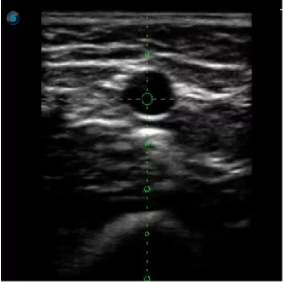

傳統(tǒng)腔內(nèi)探頭采用直柄設(shè)計,在搭配穿刺架使用時,手術(shù)空間小,不易操作;生殖專用的曲柄探頭,探頭柄采用彎曲成角度設(shè)計,可實現(xiàn)監(jiān)視、取卵兩不誤,搭載穿刺架時,可以清晰顯示穿刺針的進(jìn)針過程、深度和位置,實時監(jiān)視取卵全過程,保障取卵操作精準(zhǔn)與安全。

取卵臨床圖